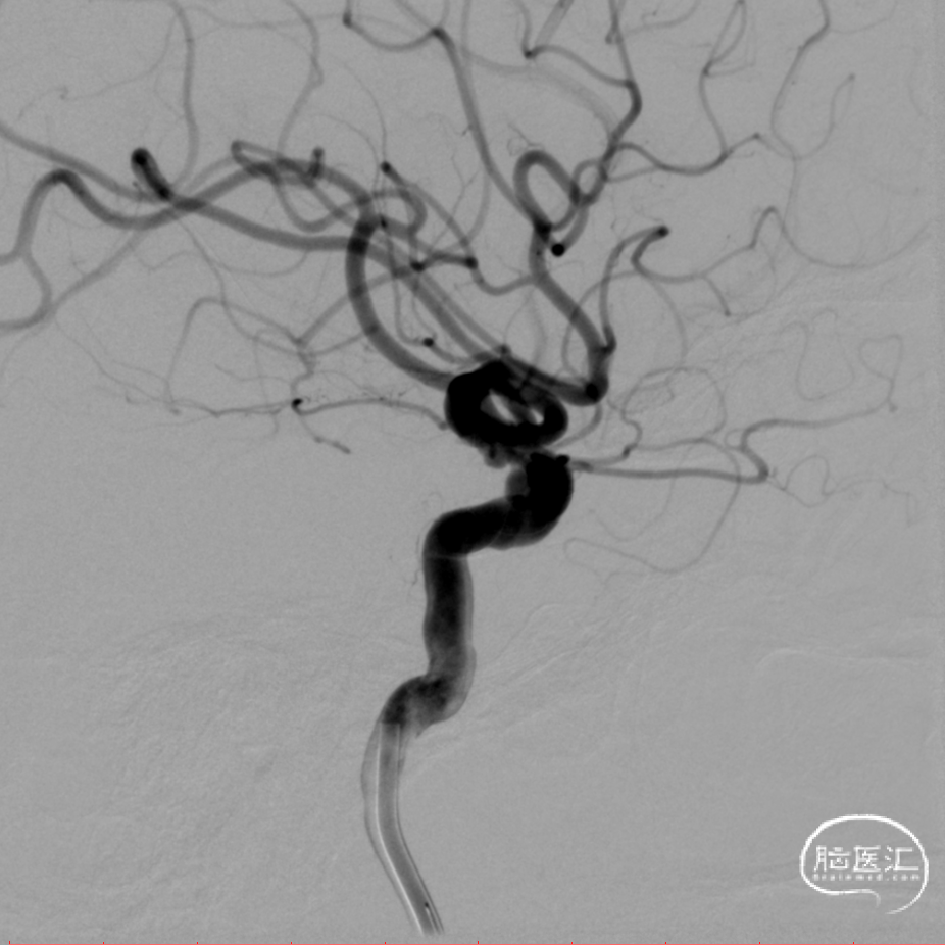

脑血管DSA(2024.08.09)

脑血管DSA

左侧颈内动脉动脉造影见动脉瘤

3D提示3枚动脉瘤

近端血管直径4.8mm、远端3.6mm